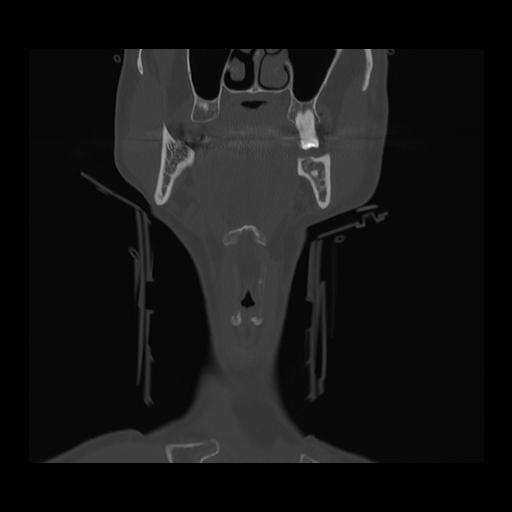

16 HUESO,,Coronal,2.000,HUESO,Coronal,